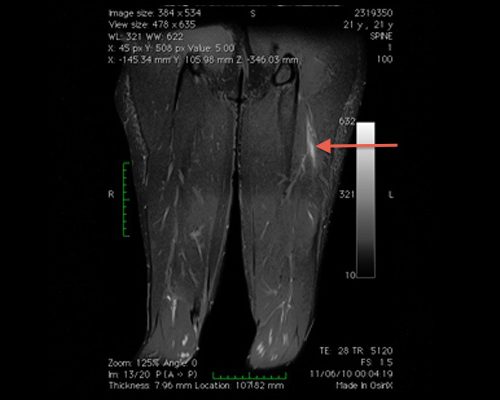

Lesão muscular da cabeça curta do bíceps.

Atleta de 21 anos com dor súbita na coxa durante corrida de velocidade. Lesão muscular grau 2 na cabeça curta do bíceps (corte coronal STIR)